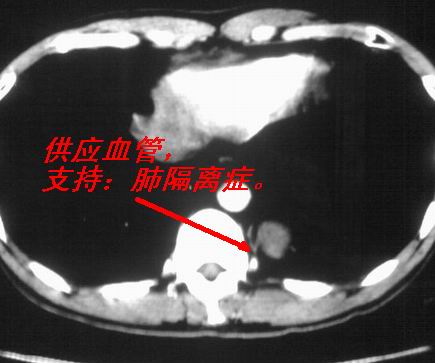

以下是引用苯小孩在2007-4-24 19:46:00的发言:[br]左下肺内侧基底段,见类圆形病灶,边缘清晰光滑.强化后轻中度强化.<平扫第4层面似有从腹主动脉相连血管影,可惜强化扫描这层没有抓住>考虑:左下肺隔离症.建议dsa或薄层强化重建观察.

以下是引用同在2007-4-24 20:11:00的发言:[br]考虑肺隔离症